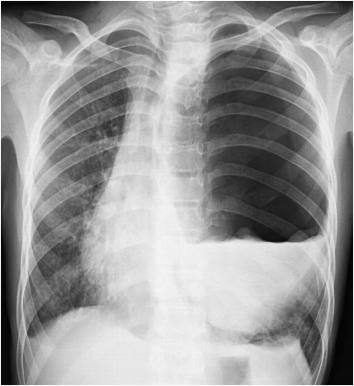

胸部X线片显示左侧

图1 胸部X光片显示左侧张力性气胸,同时纵隔向右移位。

左侧可见“水浮莲征”提示可能存在破裂的包虫囊肿。